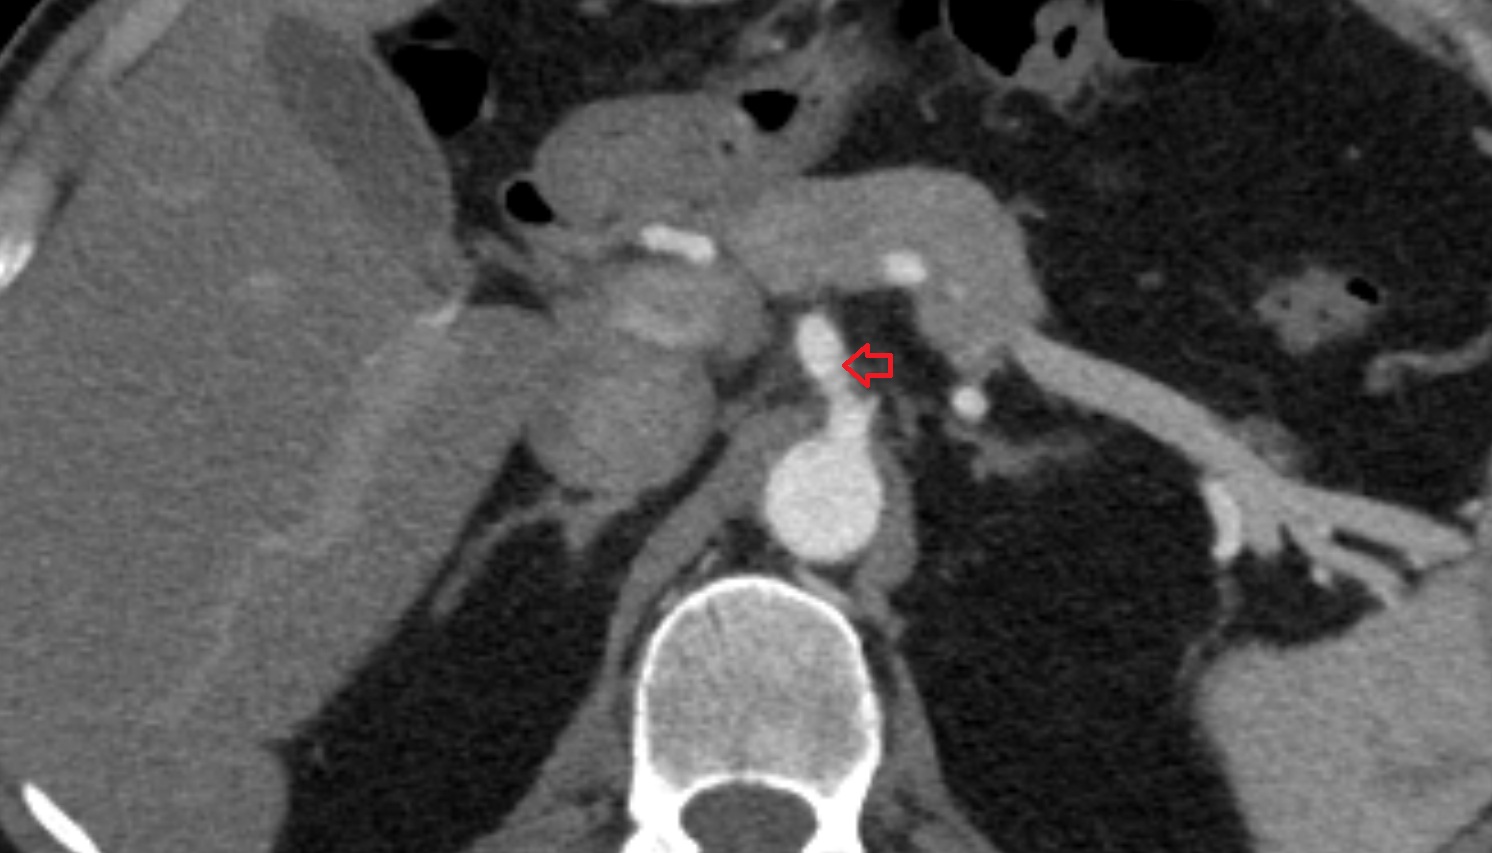

- Hepatic portal vein

- Superior mesenteric artery (SMA)

- Renal artery

- Renal vein

- Left renal artery

- Right renal artery

- Neck of pancreas

- Head of pancreas

- Uncinate process of pancreas

- Body of pancreas